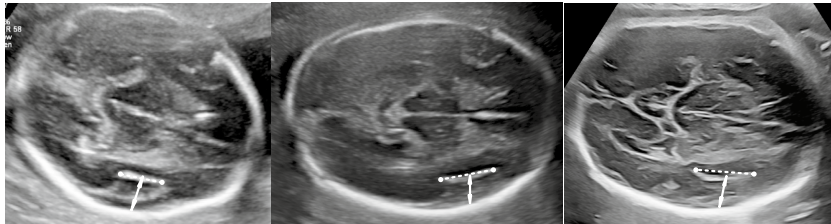

本研究针对胎儿大脑外侧裂(SF)异常筛查的临床难题,开发了基于二维超声的定量参数——外侧裂比值(SFR),通过前瞻性测量128例正常胎儿和38例异常病例,建立22-31孕周的SFD、SFW和SFR参考曲线。研究发现SFR>0.7(22-24周)和>1(25周后)可作为筛查阈值,对皮质发育异常(MCD)的检出率达100%,为临床提供了一种简便可靠的筛查工具。

在产前诊断领域,胎儿大脑外侧裂(Sylvian fissure, SF)的发育评估一直是神经超声检查的难点。作为大脑外侧最显著的解剖标志,SF的成熟过程被称为"盖化"(operculization),其异常往往提示严重的皮质发育异常(Malformation of Cortical Development, MCD)或神经元迁移障碍。然而现有评估方法存在明显局限:单纯测量SF深度(SFD)缺乏全面性,三维超声操作复杂,冠状切面难以获取,而主观形态学评估则高度依赖操作者经验。这些技术瓶颈使得临床亟需一种客观、简便的定量筛查方法。

为突破这一困境,首都医科大学附属北京妇产医院超声科的研究团队开展了一项创新性研究。通过前瞻性纳入128例正常胎儿(对照组)和38例经MRI确诊的SF异常胎儿(研究组),团队在22-31孕周(GA)期间系统测量了SF深度(SFD)、宽度(SFW),并首创性地提出外侧裂比值(SFR=SFW/SFD)这一新参数。研究采用多项式回归构建了各参数与GA的参考方程:SFD(mm)=-1.48GA2